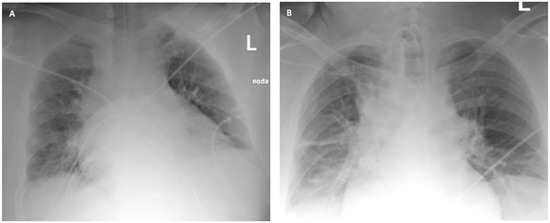

The ICU team used NIV through an oronasal mask in PS/CPAP mode with FiO2 of 1.0. Due to the increasing symptoms of respiratory failure (PaO2 = 61 mmHg, PaCO2 = 66.6 mmHg), dyspnea, and tachypnoea >40 BPM, as well as significant respiratory effort and disturbances of consciousness, the patient was intubated, and 4 h after admission to the ICU, mechanical ventilation was initiated in the SIMV (PC) mode with FiO2 of 0.9, PEEP = 13 cmH2O, Pins = 24 cmH2O, Cdyn = 46 mL/cmH2O, Pplat = 21 cmH2O, obtaining optimal MV [14]. Deep hypoxemia with a PaO2/FiO2 ratio <60 was observed. An infectious disease specialist did not qualify the patient for treatment with remdesivir. Multimodal deep analgosedation was included. Dexamethasone IV at a dose of 6 mg, as per NIH guidelines, and therapeutic doses of low-molecular-weight heparin were used [12]. LUS imaging showed a bilateral B-profile and massive basal consolidations. The cardiac ultrasound demonstrated the proper function of the right and left ventricles, and no valvular changes were recorded. On day 2 from the initiation of the mechanical ventilation, the prone position maneuver was attempted; however, it was unsuccessful due to the difficulties related to the patient’s abdominal obesity. Additionally, numerous recruitment maneuvers were used, consisting of inspiration extended to 20 s with Pplat up to 30 cmH2O, performed twice, without improvement in oxygenation or increase in Cdyn. On day 4 of the ICU stay, due to PaO2/FiO2 ratio <60, a decision was made to use VV ECMO. The calculated RESP score was 4, with a class II risk and an estimated ECMO survival probability of 76%. Before cannulation, the patient underwent percutaneous Griggs tracheostomy. The implantation technique and cannulation equipment used were identical to those described in Case 1. The correct position of the cannulas was confirmed by ultrasound examination and chest X-ray (Figure 4).

Figure 4. Chest X-ray: (A) after admission to the ICU; (B) 2 days after starting VV ECMO treatment (Case 2).